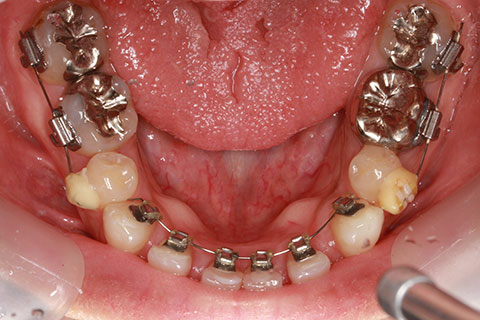

ハーフリンガル矯正3:上の歯のみ舌側矯正で治療(矯正期間24ヶ月)

治療前

治療中(開始直後)

治療中(開始半年後)

治療後

- 年齢・性別

- 25歳女性

- 治療期間

- 2年0ヶ月

- 抜歯

- 上下4番抜歯

- 治療費

- 110万円

- 治療内容

- 施術の副作用(リスク)

- 表側矯正と比較して、力学的な操作性が複雑なため、ボーイングエフェクトを起こしやすい。